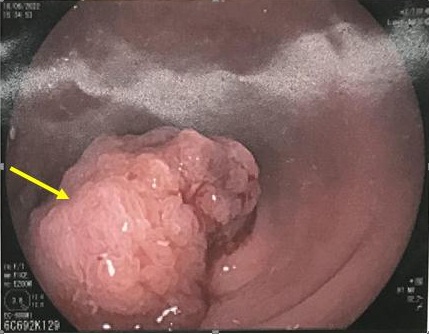

Hình ảnh polyp trực tràng kích thước 2,0×2,5cm (mũi tên màu vàng) ở bệnh nhân nam, 68 tuổi. Kết quả giải phẫu bệnh sau khi cắt polyp là ung thư biểu mô tuyến biệt hóa vừa.